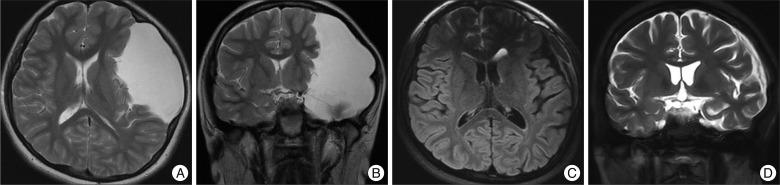

The indications and optimal surgical treatments for intracranial cysts are controversial. In the present study, we describe long-term clinical and neuroimaging results of surgically treated intracranial cysts in children. The goal of this study is to contribute to the discussion of the debate.

This study included 110 pediatric patients that underwent surgeries to treat intracranial cysts. Endoscopic cyst fenestrations were performed in 71 cases, while craniotomies and cyst excisions (with or without fenestrations) were performed in 30 patients. Cystoperitoneal shunts were necessary for nine patients. Long-term results were retrospectively assessed with medical and neuroimaging records.

Clinical and radiological improvement was reported in 87.3% and 92.8% of cases, respectively, after endoscopic neurosurgery, and in 93.3% and 100% using open microsurgery whereas 88.9% and 85.7% after shunt operation. There were no statistical differences in clinical outcomes (p=0.710) or volume reductions (p=0.177) among the different surgeries. There were no mortalities or permanent morbidities, but complications such as shunt malfunctions, infections, and subdural hematomas were observed in 56% of the patients that had shunt operations. A total of 13 patients (11.8%) underwent additional surgeries due to recurrences or treatment failures. The type of surgery performed did not influence the recurrence rate (p=0.662) or the failure rate (p=0.247).

Endoscopic neurosurgeries are less invasive than microsurgeries and are at least as effective as open surgeries. Thus, given the advantages and complications of these surgical techniques, we suggest that endoscopic fenestration should be the first treatment attempted in children with intracranial cysts.